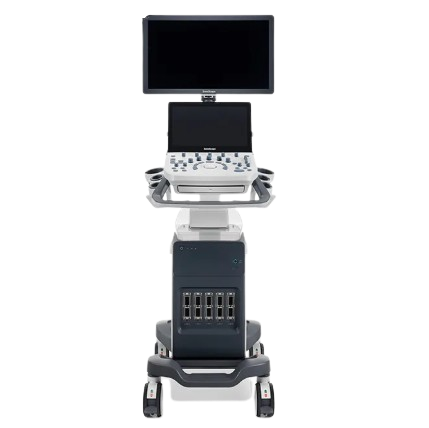

SonoScape p9 Ultrasound Machine

SonoScape P9 Color Doppler Ultrasound Machine is a high-performance diagnostic imaging system offering excellent image quality, advanced Doppler features, and durable design. Ideal for hospitals and diagnostic centers, it is available at the best ultrasound machine price in Bangladesh with special discount offers.

- Product Name: Ultrasound Machine

- Brand: SonoScape

- Model Number: P9

- Origin: China

The SonoScape P9 Color Doppler Ultrasound Machine is a premium-quality diagnostic imaging solution designed for hospitals, clinics, diagnostic centers, and medical professionals in Bangladesh. Manufactured by SonoScape, one of the world’s most trusted ultrasound brands, the P9 model delivers outstanding image clarity, advanced Color Doppler technology, and reliable performance at a low price in Bangladesh.

If you are searching for the best ultrasound machine price in Bangladesh, the SonoScape P9 stands out for its perfect balance of performance, durability, and savings. This Color Doppler Ultrasound Machine BD is suitable for abdominal, OB/GYN, cardiac, vascular, small parts, and musculoskeletal examinations. It is widely used by leading hospitals and diagnostic centers in Dhaka and across Bangladesh.

The SonoScape P9 is engineered to meet the growing diagnostic demands of modern healthcare facilities. With intelligent imaging algorithms and a powerful processing system, it produces crystal-clear images that help doctors make accurate clinical decisions.

Product Specifications

-

Product Name: Ultrasound Machine

-

Brand: SonoScape

-

Model Number: P9

-

Type: Color Doppler Ultrasound Machine

-

Origin: China

-

Display: High-resolution medical display

-

Applications: Multi-purpose diagnostic use

-

Availability: Ready stock in Bangladesh